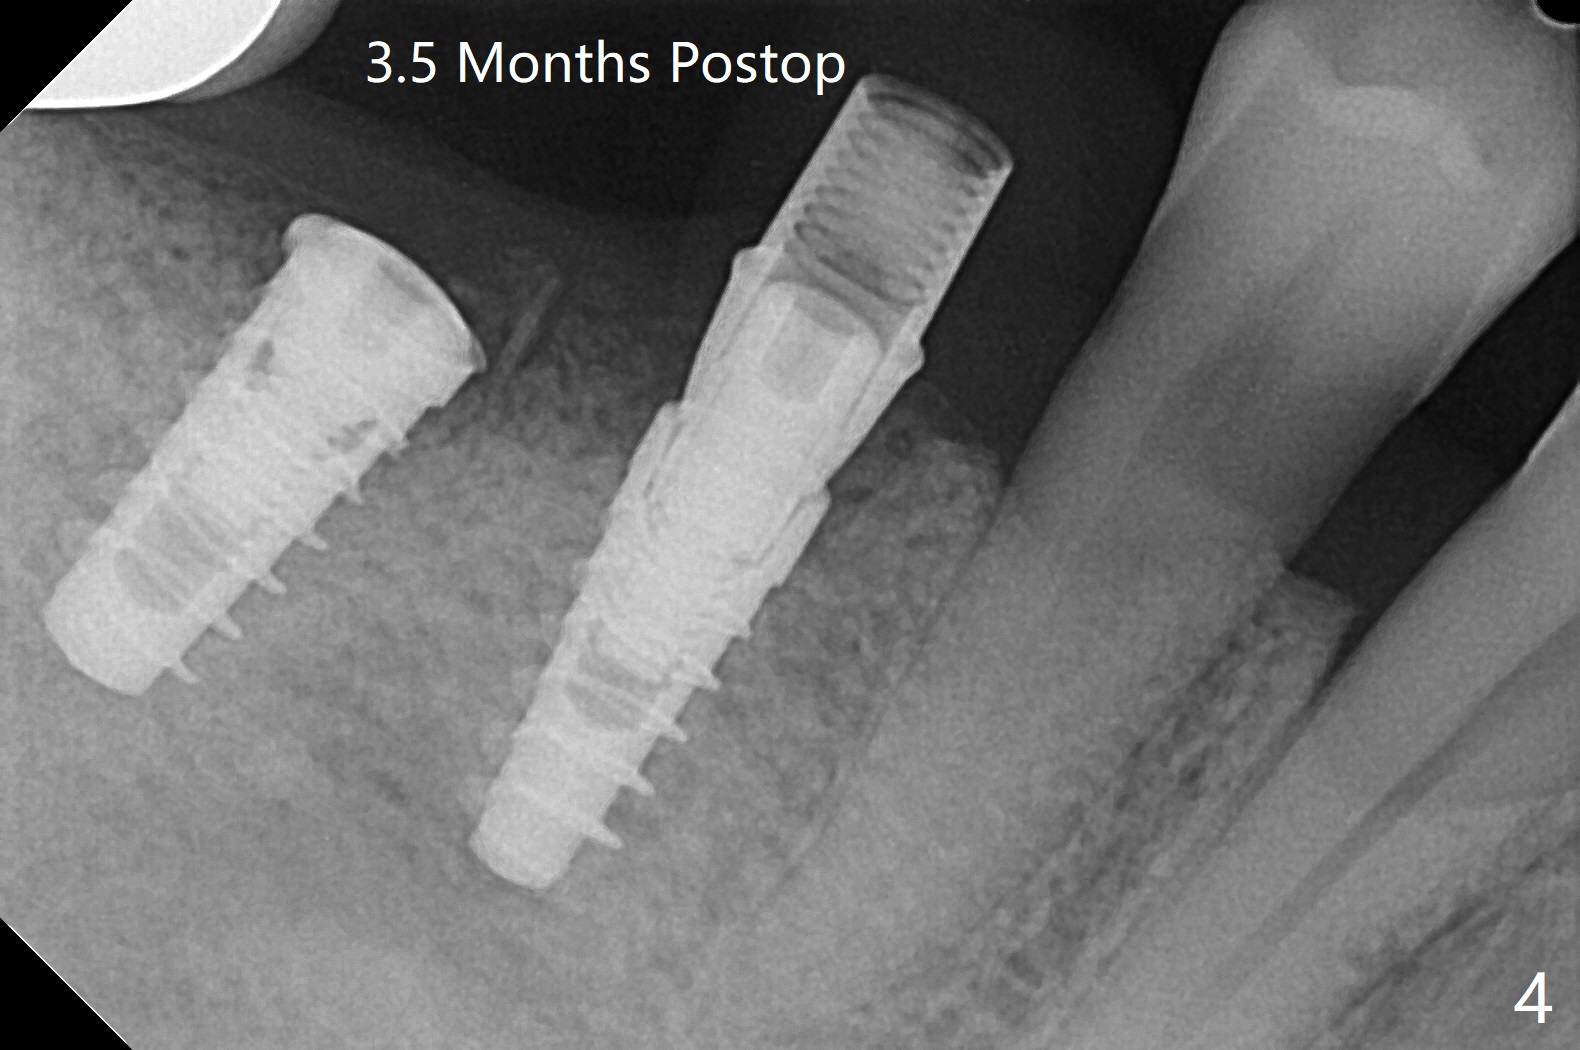

右下5,6植体植入后,取下导板,发现两者都植入不够深,放回导板,5植体植入深点(35Ncm),但是6植体与植牙工具通过导板接不上,正好取出导板,徒手旋紧,不幸的是植体往近中移位(图一:空箭头,远离中隔(S)),稳定性好像降低,不适合即刻修复,放置愈合螺帽后,大量植入粘性骨粉,包括进入7近中(短箭头,事先需要往上分离龈乳头),覆盖PRF膜,PGA缝线,利用5基台,固定树脂敷料。术后5个星期,撤除树脂敷料,虽然愈合螺帽暴露,周围牙龈健康,并含有骨粉(图二)。术后两个月植体基本被覆盖(图三),术后3.5个月植体完全覆盖,切开前根尖片显示植体平台与牙槽嵴平齐(图四),术中证实。5基台好像没有就位(图四(可能拍摄角度不佳)),将基台平面从远中旋转至颊侧,就位仿佛改善(图五)。术后四个月6放置基台后(图六),制作连体5,6牙冠,垫高(打开咬合),近中衬里,推4,关闭3,4之间间隙(图三)。6植体远中第一个螺纹好像暴露。